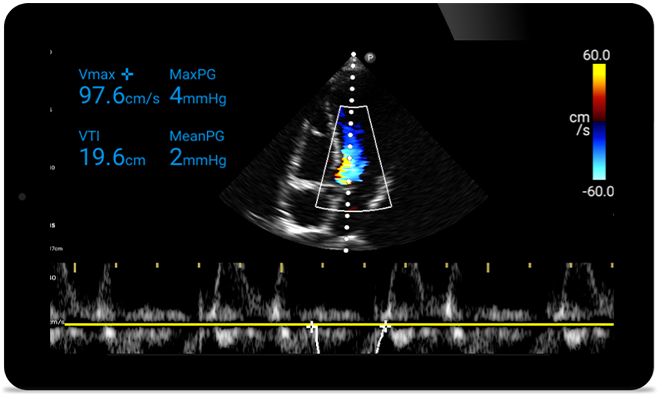

Act faster to protect their heart

When seconds count, portable ultrasound can make the difference. Lumify can provide the high-definition imagery you need whenever and wherever you need it.

Opportunity to potentially reverse cardiomyopathy

Tutorial

Intro to transthoracic echocardiography